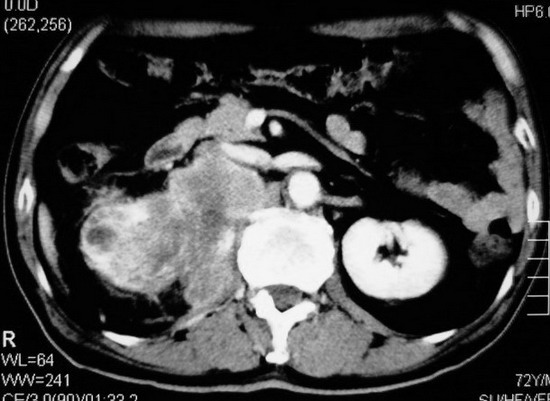

以下是引用杀毒软件在2008-11-17 19:15:00的发言:[br]考虑------右肾癌合并肾静脉---同侧肾上腺受侵可能性大

以下是引用zjzjr在2008-11-17 20:45:00的发言:[br]考虑------右肾癌合并肾静脉---同侧肾上腺受侵可能性大及腹膜后淋巴结转移.